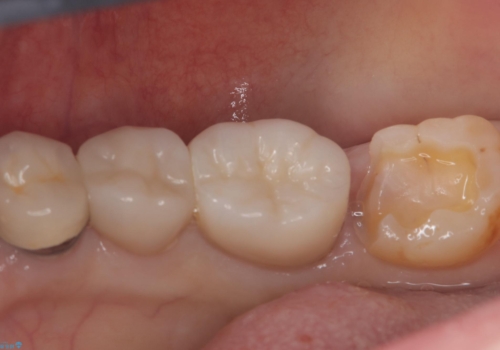

- 主訴:下の歯に詰まっている銀が笑うと見えて嫌だから白くしたい

右下7番目の歯に保険適用のメタルインレーが入っており、大きなう蝕などは認めなかったため概形は大きく変えずセラミックインレーへやり替えとなりました。

やり替える過程で古い裏層材やカリエスは全て除去し、新たにCR裏層を行っています。

セラミックインレーセット時はラバーダム防湿を行っています。